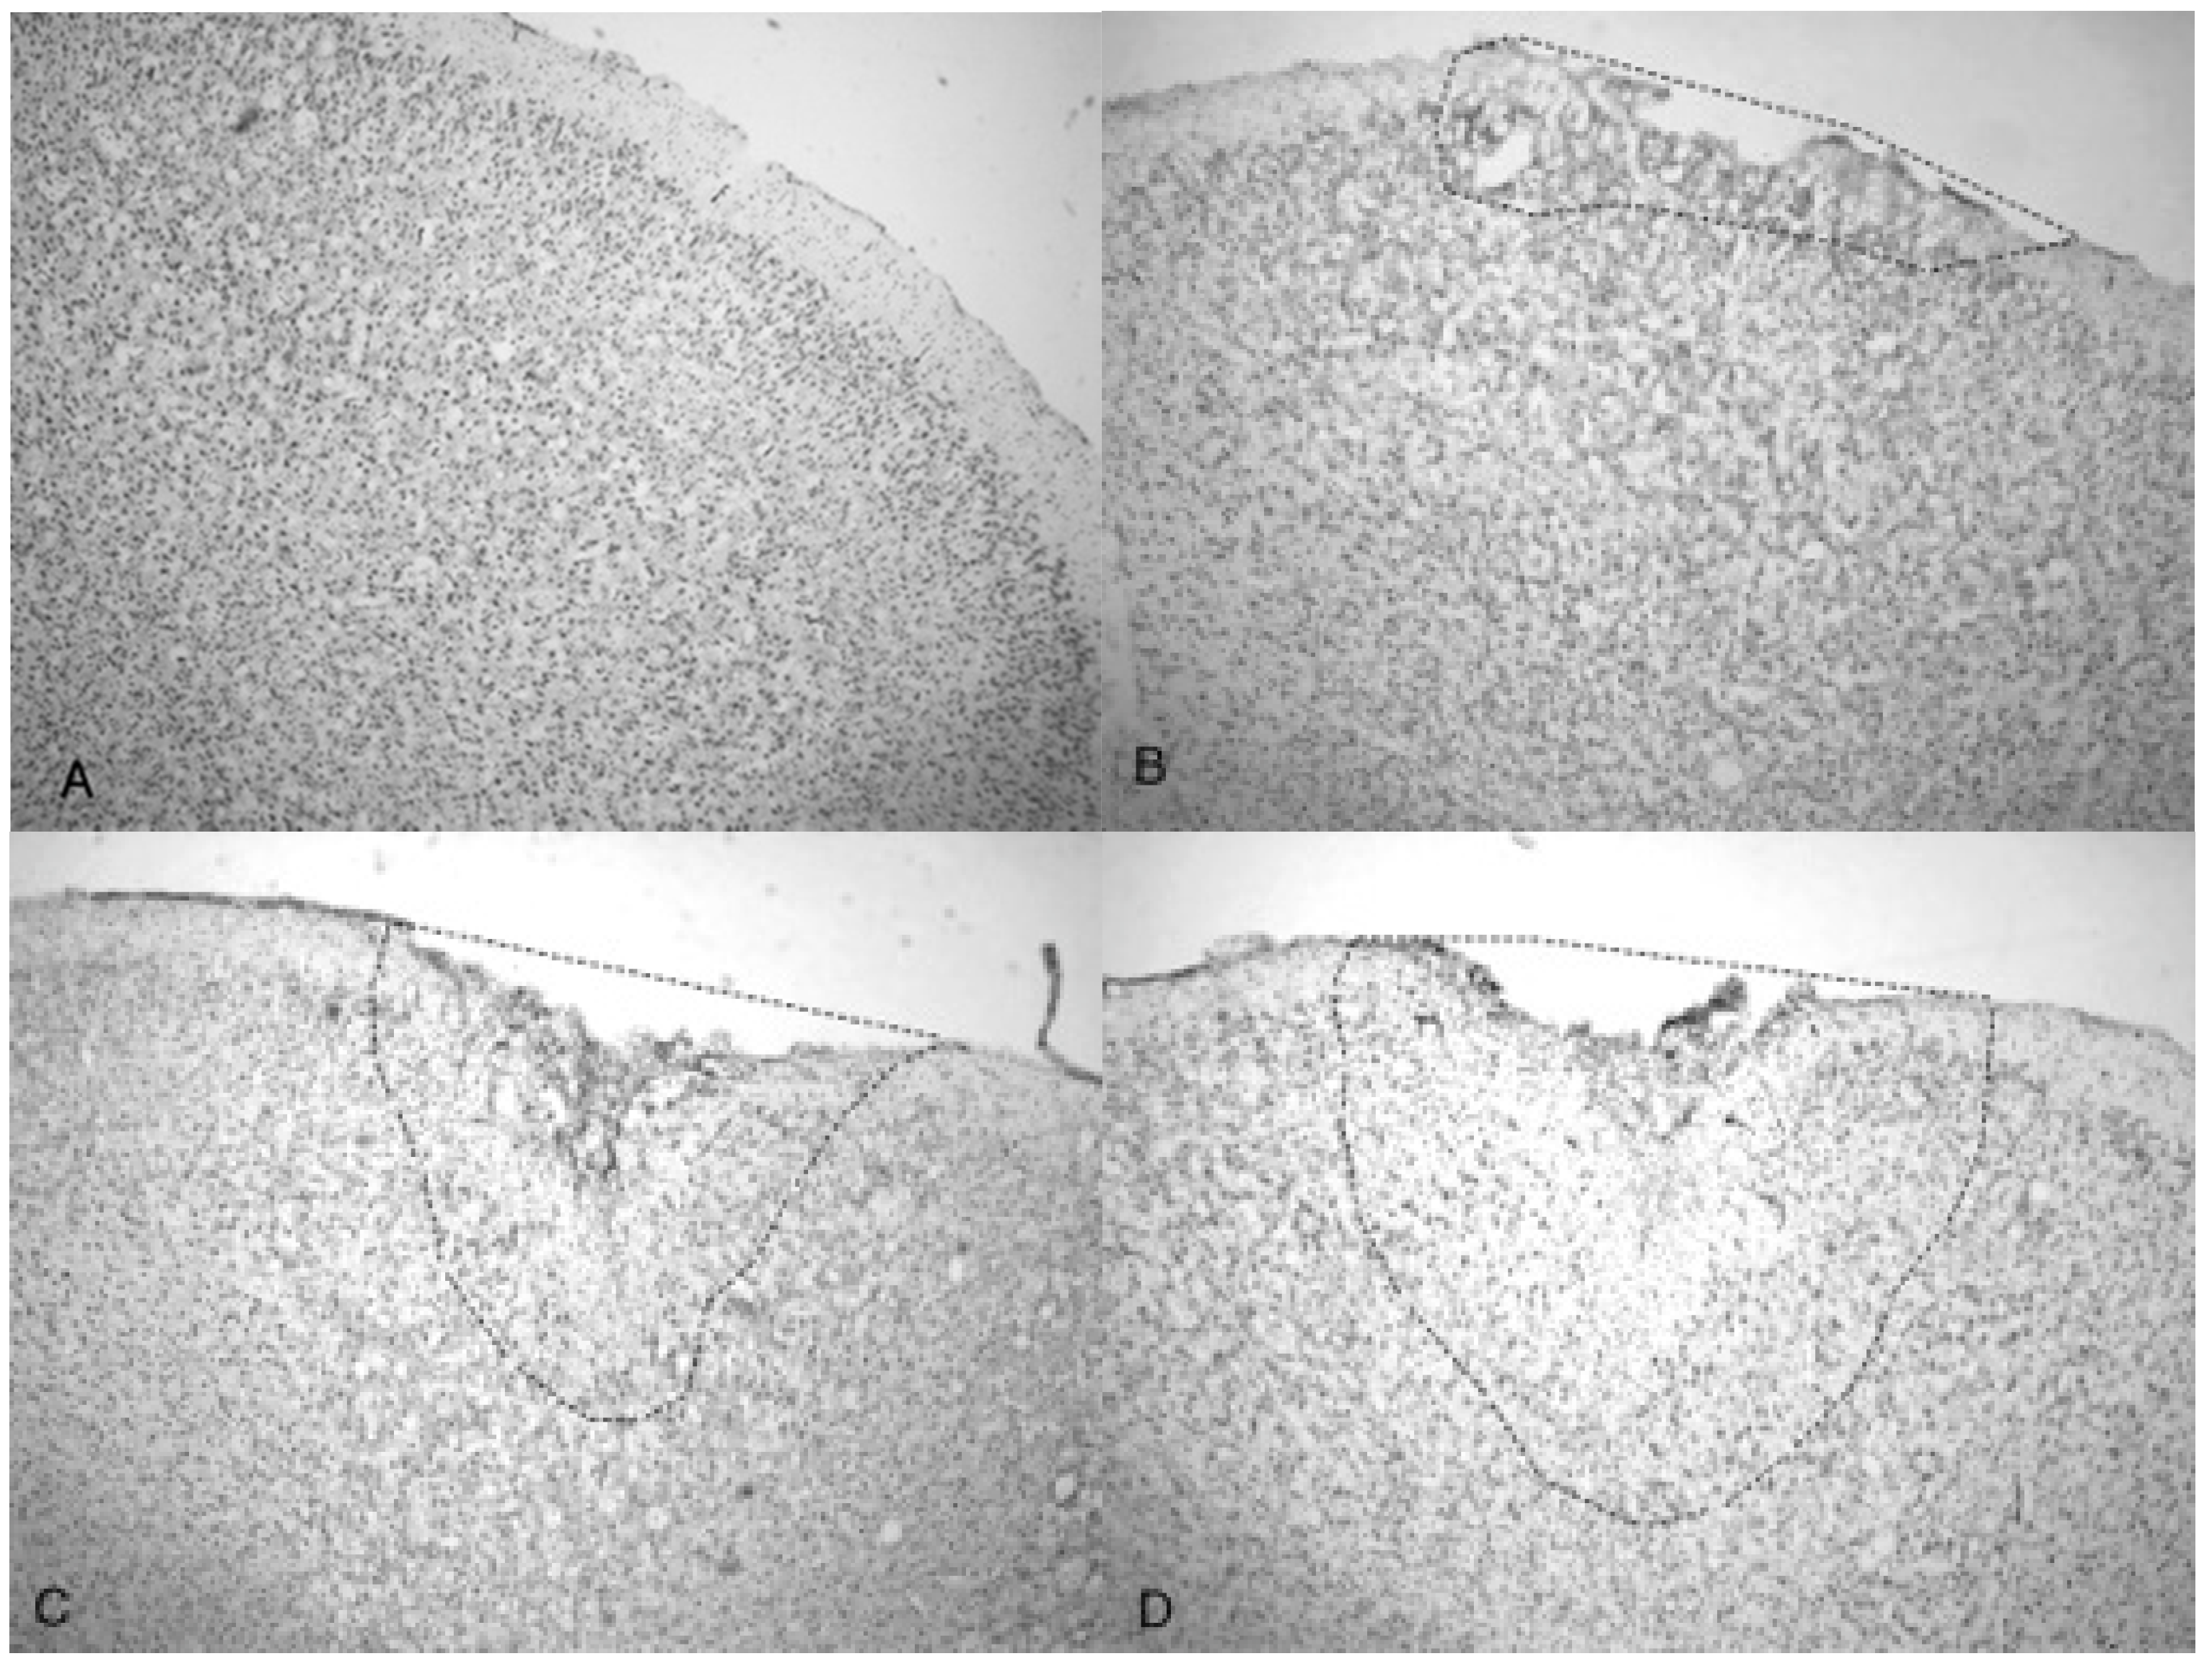

A side-by-side comparison of all four treatments is shown in Figure 6. An intact, uninjured cortex revealed no detectable damage (Figure 6A). Slight damage of the outer cortex that does not penetrate beyond the pia mater is seen in the 3.4 bar treatment (Figure 6B). The injury from the 4.2 bar treatment is much more significant than that of the 3.4 bar, penetrating beyond the pia mater and reaching cortical neurons (Figure 6C). The depth of the 4.2 bar injury can be compared to that of the 5.0 bar injury (Figure 6D). The 5.0 bar treatment is much more pervasive and penetrates even deeper into the cortex. The clearer space within the marked region (Figure 6D) clearly shows neuronal cell death.

Finally, the depth of TBI-induced injury was analyzed from the tissue slices from the 3.4, 4.2 and 5.0 bar treatment groups. The damaged cortical area from each animal was traced and outlined (see Figure 6), and a mean injured area was determined (Figure 7). The 3.4 bar treatment group had an average injury area of 1.07 mm 2. The 4.2 bar treatment group had an average injury area of 4.36   mm 2 nearly four times greater than damage caused by the 3.4 bar treatment. Finally, the 5.0 bar treatment group had an average injury area of 8.15   mm 2 which was nearly eight times greater than the 3.4 bar and nearly two times greater than the 4.2 bar injury. An ANOVA showed statistical differences among the treatment groups (F = 134.90; p < 0.001) in a dose-dependent manner.

Figure 6. Photomicrographs taken of the frontal cortex showing the overall depth of injury and due to the penetration of acoustic waves: the control (0 bar), 3.4, 4.2 and 5.0 bar TBI, respectively of Han-Wistar rats, ten days post-injury. Image (A) shows no damage from an untreated, control rat (0 bar). Image (B) shows slight damage to the outer cortex (3.4 bar). Images (C,D) show the deeper penetrating impact delivered by the 4.2 and 5.0 bar. The dotted lines show examples of the infarct boundaries traced by locating the perimeter of condensed dark cells used to calculate the expanse of the area damaged. All images were taken at 40× magnification.

The increasing size of the TBI is dependent on acoustic wave intensity and can be observed in Figure 6 and Figure 7, implicating the scalable nature of the Storz-D-Actor acoustic wave, produce a mild TBI (Figure 6B) or a more intense moderate TBI (Figure 6C,D). Although not part of this research, the Storz-D-Actor could conceivably produce a more severe TBI with repeated applications, resulting in much greater cell death. While disruption and fragmentation of the dura mater seemed consistent throughout the test groups, wave intensity correlated to both the size and depth of TBI (Figure 6 and Figure 7). Subsequent measurements of TBI infarct area (Figure 7) corroborate the visual evidence in the photomicrographs. TBI injury causes pyknosis, defined as when neurons condense and become darkly stained cells [33,34]. Other studies have observed similar results with dark neurons expressing apoptotic proteins Bax, BCl2 and cleaved caspase-3 [28]. Other experiments have identified the presence of jellyfish microglia that are activated after TBI insult and are part of the inflammatory process responsible for neuroprotection and reparative are cells, aiding in neuronal recovery [35].